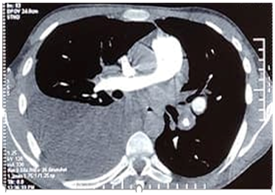

A 21-year-old man was followed for six months in the internal medicine department for Hughes-Stovin syndrome. He presented with pulmonary arterial aneurysms (Figure 1) thrombosis of the hepatic and inferior vena cava veins and recurrent bipolar aphthosis. The patient was treated with colchicine mg per day, oral corticosteroid 60mg per day and monthly boli of cyclophosphamide. The evolution was marked by the occurrence of a state of epilepticus complicated by inhalation pneumopathy due to Staphylococcus Aureus requiring intubation and mechanical ventilation for eight days in intensive care unit. Status epilepticus could not be explained by metabolic, toxic, infectious or iatrogenic causes. There was no concept of trauma and the brain scanner was without abnormalities. Magnetic resonance brain imaging with gadolinium injection showed no parenchymal or vascular lesions. The electroencephalogram showed a non-abnormal pattern. An improvement in the neurological state with no seizure recurrence was obtained under anti-epileptic treatment. The pulmonary examination showed clinical improvement and radiological cleansing. Two weeks later, the patient experienced chest pain with acute dyspnea. The examination found an increase in the sonorityduring percussion of the thorax with a decrease in respiratory sounds in auscultation. Chest X-ray and thoracic computed tomography scan showed the presence of a left medium-sized pneumothorax (Figure 2A), associated with fusiform aneurysmal dilatationof the apical branch of the Lingula (Figure 2B), and posterolateral atelectasis of the left lower lobe containing pneumatocele blebs. The pneumothorax extended rapidly and became bilateral. The patient was transferred to a resuscitation unit undergoing a chest drainage. The course was marked by severe respiratory distress requiring intubation.The patient had died with an unexplained etiology.

Figure 1 Pulmonary aneurysmsat thoracic computed tomography scan.